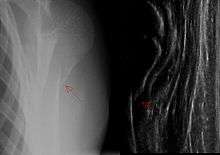

Proximal humerus fracture

In patients younger than 12, proximal humerus fractures can be visualized due to the changes at the bone surface.[15] Because bone tumors can appear at this location, X-ray imaging is necessary following a fracture diagnosis. The standard procedure is the shoulder-SAFE algorithm.[15] The sensitivity of the method in comparison with X-ray imaging is 94.4 percent, and the specificity is 100 percent.[19]